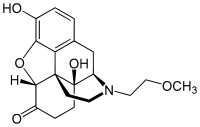

Oripavine derivatives

Thienorphine

- 7-PET

- Acetorphine

- Alletorphine (N-allyl-noretorphine)

- BU-48

- Buprenorphine

- Buprenorphine-3-glucuronide

- Cyprenorphine

- Dihydroetorphine

- Etorphine

- Homprenorphine

- 18,19-Dehydrobuprenorphine (HS-599)

- N-cyclopropylmethylnoretorphine

- Nepenthone

- Norbuprenorphine

- Norbuprenorphine-3-glucuronide

- Thevinone

- Thienorphine

Structures

| Oripavine derivatives | ||||

|---|---|---|---|---|

7-PET 7-PET |

Acetorphine Acetorphine |

Alletorphine Alletorphine |

BU-48 BU-48 |

Buprenorphine Buprenorphine |

Cyprenorphine Cyprenorphine |

Dihydroetorphine Dihydroetorphine |

Etorphine Etorphine |

Homprenorphine Homprenorphine |

18,19-Dehydrobuprenorphine 18,19-Dehydrobuprenorphine |

N-cyclopropylmethylnoretorphine N-cyclopropylmethylnoretorphine |

Nepenthone Nepenthone |

Norbuprenorphine Norbuprenorphine |

Thevinone Thevinone |

Thienorphine Thienorphine |